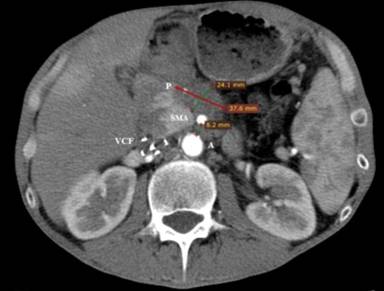

A forty-eight-year-old, male patient with significant weight loss and dyspepsia underwent diagnostic CT scan in July 2011 which revealed a tumor mass in the body of the pancreas. The tumor was histologically verified as an adenocarcinoma. It was inoperable at the time of diagnosis due to infiltration of the hepatic artery, the splenic artery and the superior mesenteric artery (Figure 1). A cycle of combined chemotherapy applications started in August 2011 and continued to December 2012. Gemcitabine (1,600 mg/m2 i.v. weekly) plus ambulatory (Erlotinib 100 mg/day p.o.) were administered in these seventeen months. Control CT scans and the evaluation of the tumor-response showed stabilization of the disease during this period.

Figure 1. Contrast enhanced CT scan at the time of diagnosis. A: aorta; P: pancreatic lesion; SMA: superior mesenteric artery |

Figure 3. Contrast enhanced CT, obtained before HIFU treatment on March 19th, 2013. The distance between the aorta (A) and the superior mesenteric artery (SMA), compressed by the tumor mass is about 8 mm. P: 38 mm hypodense tumor lesion of the pancreas; VCF: vena cava filter |